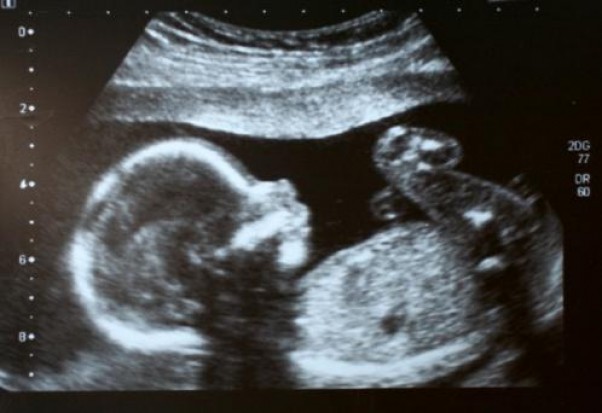

dzisiaj miałam kolejne usg ale już takie dokładne i pani doktor pozwoliła sobie na chwilę cierpliwości i złapała dokładnie twarzyczkę mojego dziecka- ma zadarty nosek :D mąż powiedział że to po mnie i że na bank będzie córeczka ale tego jeszcze nie widać :)